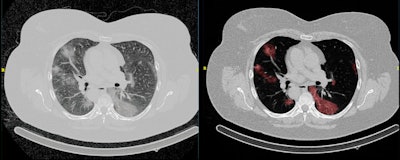

Most radiologists would welcome the support of AI algorithms for many applications, such as the detection and follow-up of lung nodules in CT exams of the chest or the analysis of total body CT scans for the detection and comparison of osteolytic lesions of 5 mm or larger in patients with multiple myeloma. These are repetitive, time-consuming tasks without much satisfaction for the radiologist.